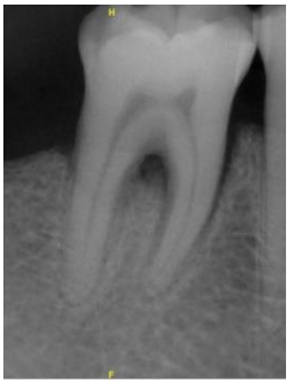

| Original Images | Gaussian High-Pass Filter | Gaussian High-Pass Filter + Mask | |

|---|---|---|---|

| Validation Accuracy | 84.16% | 87.21% | 94.97% |

| Validation Loss | 0.7634 | 0.4578 | 0.1822 |

| Model | GoogLeNet | GoogLeNet | GoogLeNet |

| Image | ![]() | ![]() | ![]() |